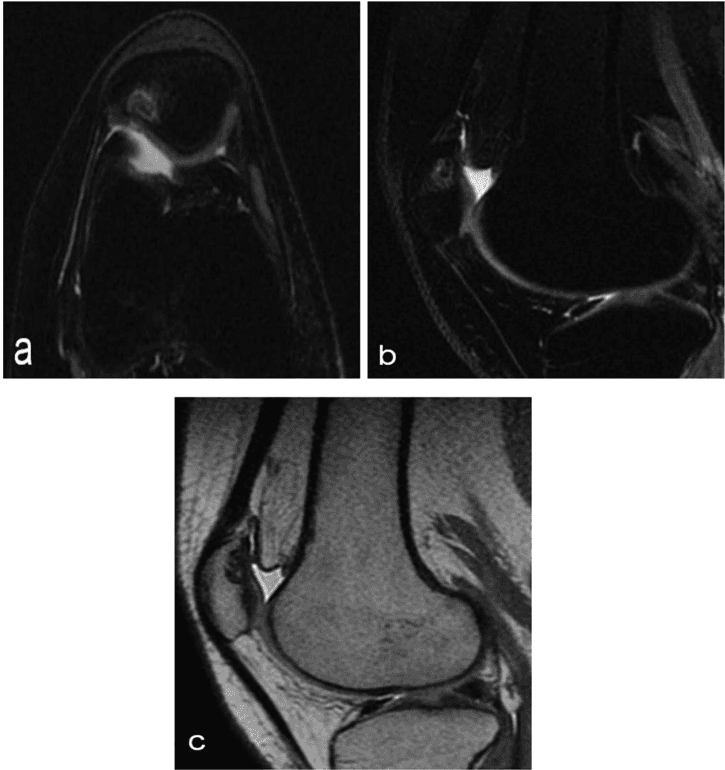

Microfragmented adipose tissue in the treatment of a full-thickness supraspinatus tear: a case report

John L Ferrell, Alanna Dodson, Joshua Martin, Future Medicine, 2023